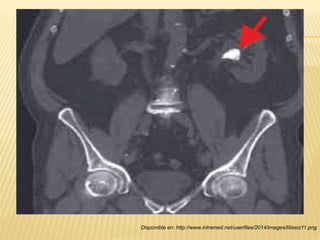

“Lito de oxalato de calcio” “Flebolito”

-Localización: Cálices renales,

pelvis renal y ensanchamientos

uretrales.

-Tamaño: 1-8 cm de diámetro.

-Composición: 100% de calcio.

-Localización: Venas pélvicas,

vejiga, genitales, próstata y otros

órganos del abdomen bajo.

-Tamaño: ½ pulgada (1.25 cm)

-Composición: Coagulo de

fibrina incrustado de sales

calcaceas, con centro traslucido.